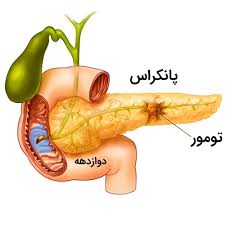

قیمت: 58٬000 تومان - دسته بندی فایل: پاورپوینتپاورپوینت پانکراس (ppt) 30 اسلاید

فروش ویژه پاورپوینت حرفه ای پانکراس / تعداد اسلاید: 30 اسلاید